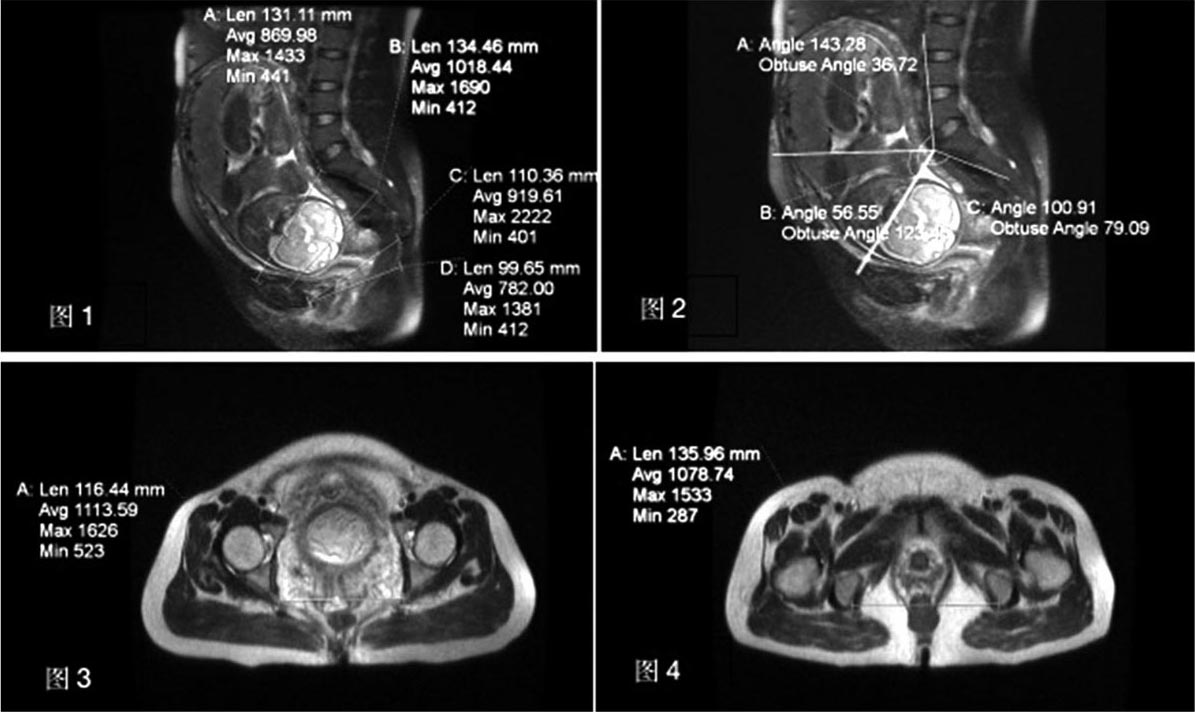

(3)磁共振(MRI)检查测量骨盆

磁共振成像提供了优于CT的对比度分辨率,且是在无电离辐射情况下进行骨盆测量。在妊娠期间尤其是中晚孕期间,MRI能够克服胎头遮挡等进行成像,弥补了超声衰减的短处,是妊娠期骨盆检查的最佳方法。Zaretsky发现MRI测量的骨盆径线与难产密切相关,但准确预测较难,Hoffmann Janine提出棘突间径≥11 cm的患者在臀先露阴道分娩中具有较高的预测价值,并建议将真结合径的底限参考值设为11 cm(图2.26)。利用MRI三维重建能实现骨盆精确的三维测量,并指导分娩体位改变,有利于阴道分娩,但仍没有一种研究表明MRI能准确筛查出头盆不称或可能发生难产的孕妇,且因价格相对较贵,对设备及测量人员要求高,目前普及范围受到较大限制。

图2.26 MRI骨盆参数

图1:

A.CV(conjugata vera):耻骨联合上缘中点至骶岬前缘正中的距离(cm)

B.PW(pelvic width):耻骨联合后方表面与第三骶椎中部之间的矢状距离(cm)

C.SOD(sacral outlet diameter):耻骨联合下缘与骶尖之间的矢状距离(cm)

D.CPO(coccygeal pelvic outlet):尾骨尖到耻骨联合下缘的矢状距离(cm)

图2:

A.PAA(pelvic aperture angle):真结合径与第一骶椎腹侧线的夹角角度(°)

B.PIA(pelvic inlet angle):真结合径与尾腰椎结合处腹面线的夹角角度(°)

C.PI(pelvic inclination):真结合径与水平线之间的角度(°)

图3:

A.ISD(interspinous diameter):坐骨棘端点之间的距离(cm)

图4:

A.ITD(intertuberous diameter):坐骨结节末端(后缘)之间的距离(cm)